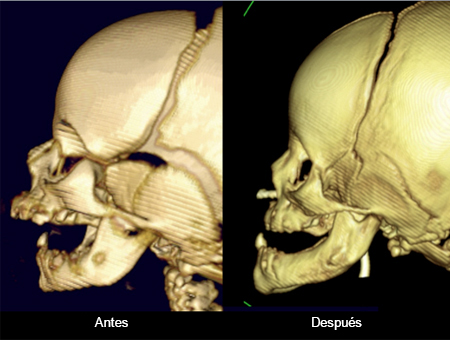

• Quienes presentan maloclusión dentofacial se someterán a septorrinoplastia definitiva con ortodoncia adicional y cirugía ortognática al alcanzar la madurez esquelética.[Figure caption and citation for the preceding image starts]: Labio y paladar hendidos unilaterales antes de la operaciónDe la colección de Travis T. Tollefson, MD, FACS [Citation ends].com.bmj.content.model.Caption@1cbc0bd1[Figure caption and citation for the preceding image starts]: Labio y paladar hendidos unilaterales después de la operaciónDe la colección de Travis T. Tollefson, MD, FACS [Citation ends].com.bmj.content.model.Caption@5f0b8ceb[Figure caption and citation for the preceding image starts]: Labio y paladar hendidos bilaterales antes de la operaciónDe la colección de Travis T. Tollefson, MD, FACS [Citation ends].com.bmj.content.model.Caption@7704f3b0[Figure caption and citation for the preceding image starts]: Labio y paladar hendidos bilaterales después de la operaciónDe la colección de Travis T. Tollefson, MD, FACS [Citation ends].com.bmj.content.model.Caption@615a4bd9[Figure caption and citation for the preceding image starts]: Labio hendido unilateral luego de la operaciónDe la colección de Travis T. Tollefson, MD, FACS [Citation ends].com.bmj.content.model.Caption@47db1913

Los neonatos que presentan secuencia de Pierre Robin (tríada de paladar hendido, microgenia y glosoptosis) pueden tener obstrucción de las vías respiratorias altas. Esta afección se trata inicialmente de manera no invasiva con posición en decúbito prono, sonda nasofaríngea o PPCVR nasal.[44] Sin embargo, hasta el 23% de los lactantes con micrognatia tienen una obstrucción relacionada con la lengua que requiere una intervención invasiva con intubación endotraqueal si la posición en decúbito prono, la sonda nasofaríngea y la PPCVR nasal no son eficaces.[45] El manejo quirúrgico de la obstrucción de la vía aérea en la micrognatia incluye la adherencia de la lengua y del labio, osteogénesis mandibular por separación (para mover la base de la lengua hacia delante y abrir las vías respiratorias) y traqueotomía que solo debe realizarse una vez agotadas todas las demás opciones.[44]

Un otorrinolaringólogo pediátrico puede realizar una evaluación de las vías respiratorias con una laringoscopia flexible para descartar otras anomalías en las vías respiratorias y manejar el reflujo laringofaríngeo asociado.[Figure caption and citation for the preceding image starts]: TC de osteogénesis por separaciónDe la colección de Travis T. Tollefson, MD, FACS [Citation ends].com.bmj.content.model.Caption@6d56f363